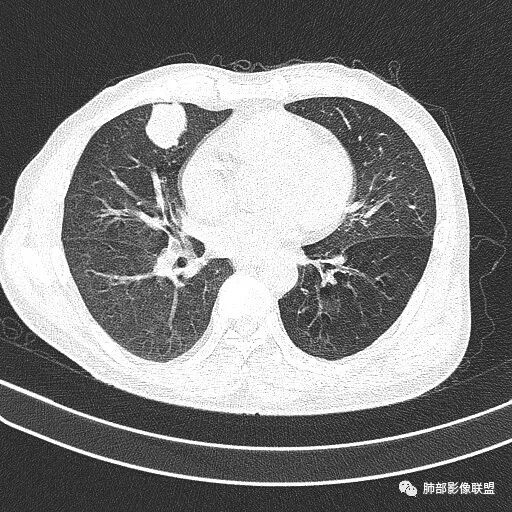

晨读病例  患者老年男性,因腰腹部疼痛3周,排尿困难1周入院。查尿常规及C反应蛋白提示泌尿系感染。肿瘤标志物NSE、细胞角蛋白19片断稍升高。胸部CT:右肺中叶内侧段类圆形肿块影,浅分叶,部分层面见深分叶,胸膜牵拉及支气管截断征象,边界清,密度低,无强化,且垮叶裂。综合考虑恶性病变,类癌及小细胞可能性大,鉴别囊肿等良性病变肺囊肿。

右肺中叶肿物,边缘光滑,呈浅分叶,周围见磨玻璃影,末端支气管截断,增强无明显强化,定性恶性,不典型类癌

薇:各位老师,下面是该病例的横断位薄层

1.右肺中叶孤立不规则块影,浅分叶,未见液化或钙化,未见毛刺,未见脐凹,未见明显胸膜牵拉。

2.近肺门侧隐约见支气管截止。